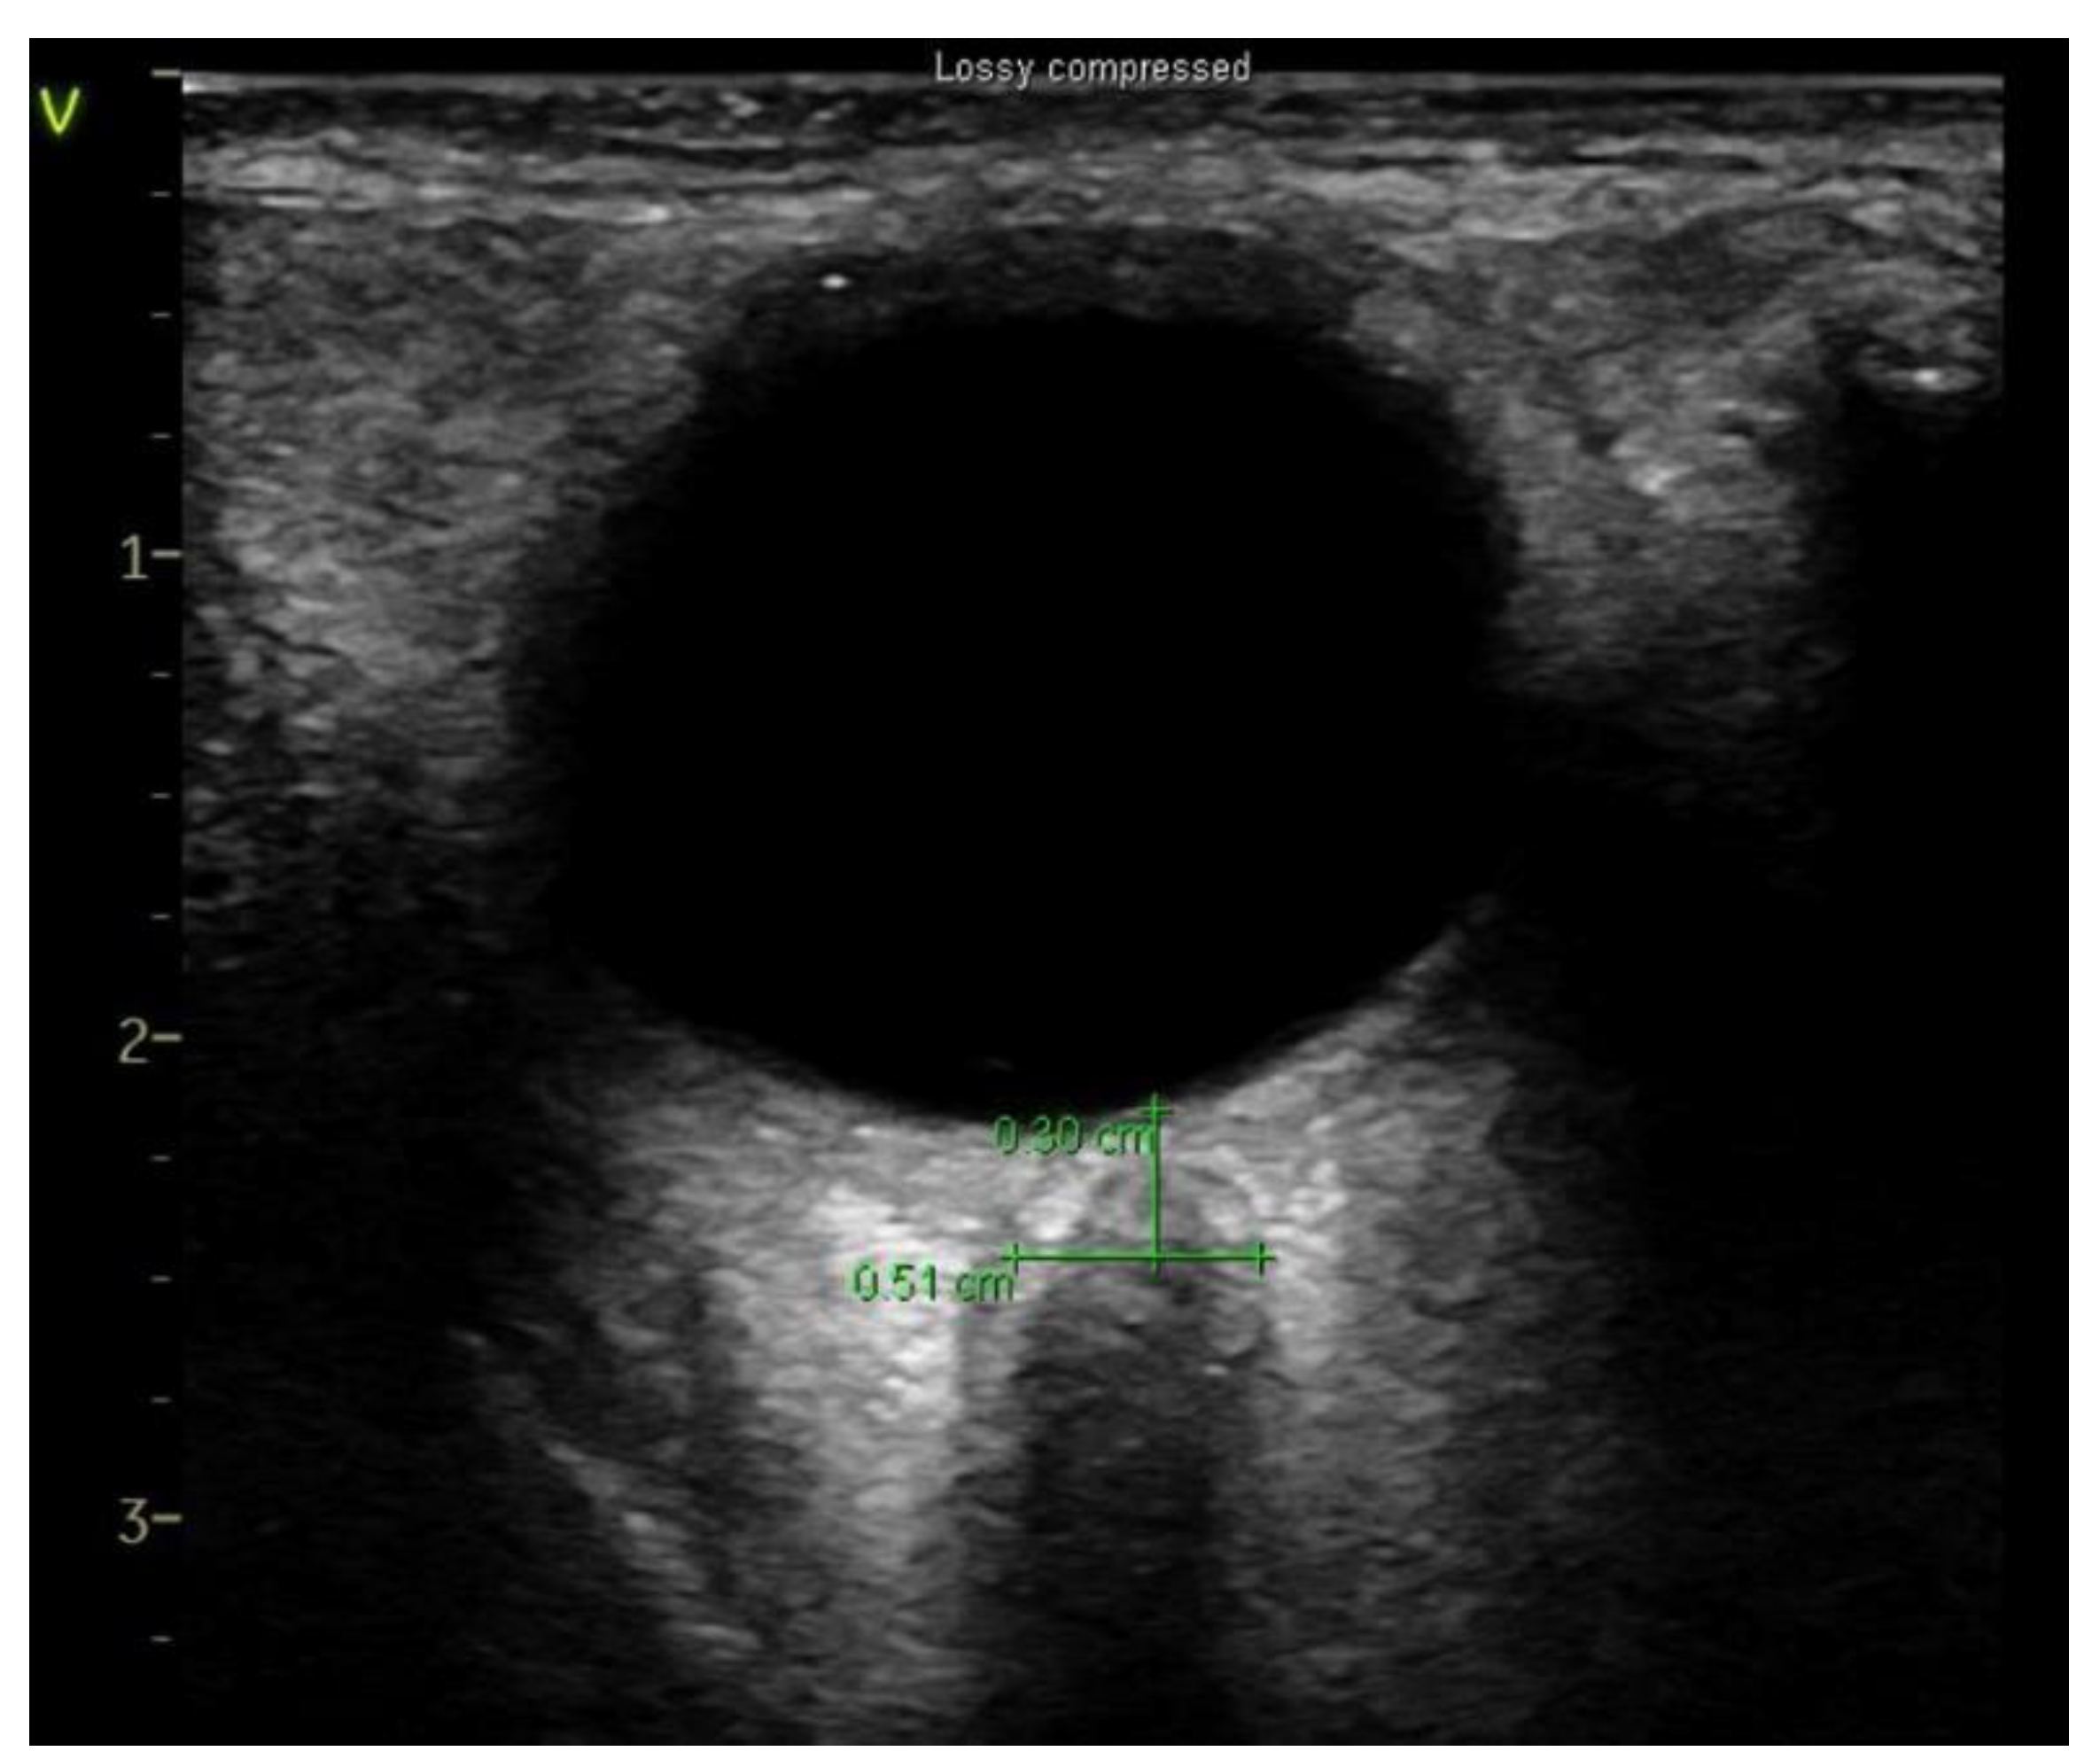

A single experienced investigator who has performed > 50 scans measured ONSD using a portable US unit (Sonosite X-Porte, Fujifilm Sonosite, Bothell, WA, USA) with a 5–10 Hz linear probe [16]. When general anesthesia induced and hemodynamically stable conditions were reached, ultra-sonographic measurements were taken. After applying water soluble lubricant, the probe was placed on the closed upper eyelid with minimal pressure in a direction parallel to the eyelid. Three measurements were acquired in the transverse plane of each eye at four timepoints (Figure 1): T0, 10 min after the induction of anesthesia in the supine position; T1, 10 min after introducing pneumoperitoneum (13 mmHg of insufflation pressure) in the steep Trendelenburg position (45° incline); T2, 10 min after releasing the pneumoperitoneum in the steep Trendelenburg position (45° incline); T3, 10 min after position change to a supine position.

Figure 1.

Sonographic optic nerve sheath diameter (ONSD).

Ultrasonographic images were reviewed using a picture archival and communication system (PACS, Centricity Enterprise Web version 3.0; GE Healthcare, Milwaukee, WI, USA) and ONSD was measured 3 mm behind the globe by the blinded two clinicians. After obtaining the mean ONSD of each eye, the mean value of ONSD in both eyes was calculated. We defined ∆ONSD as follows: ∆ONSD = 100 × (maximum ONSD at any time point—ONSD at baseline)/ONSD at baseline.